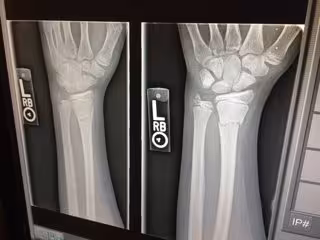

Un estudio realizado en China ha confirmado que los antecedentes de familiares de primer grado con diabetes están relacionados con un aumento de la densidad mineral ósea (DMO) y de la resistencia a la insulina. Cuanto más alto es el contenido mineral óseo, mayor es la densidad de los huesos. Y cuanto más densos son los huesos, generalmente son más fuertes y menos propensos a fracturarse.

La asociación entre la diabetes tipo 2 y el aumento del riesgo de fractura está bien documentada. Sin embargo, se sabía poco sobre el posible efecto de los antecedentes familiares de diabetes en la DMO. Debido a que los pacientes con diabetes tipo 2 tienen un mayor riesgo de fractura, comprender la fisiopatología temprana de la DMO alterada podría ser crítico en el desarrollo de estrategias preventivas para la osteoporosis diabética.

En este nuevo estudio, que involucró a casi 900 mujeres posmenopáusicas normoglucémicas, se encontró que la DMO de la columna lumbar y el cuello femoral fue significativamente más alta en participantes con antecedentes familiares de diabetes de primer grado que en aquellos sin dichos antecedentes, incluso en mujeres con niveles normales de glucosa en sangre. Estos mismos participantes mostraron además una mayor resistencia a la insulina y a la hiperinsulinemia.